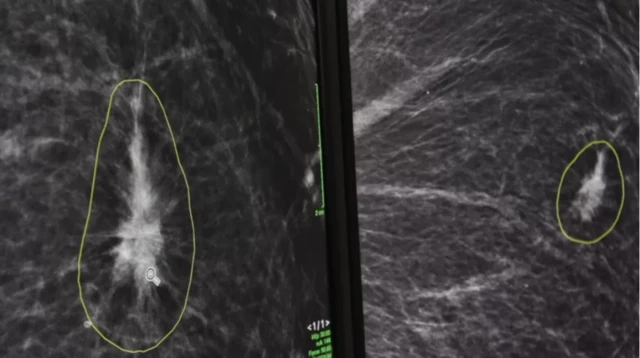

ဒီအေအိုင်ဟာ ယခင် အမည်မဖော်ထားတဲ့ ရင်သားဓာတ်မှန်တွေနဲ့ စစ်ဆေးချက် ရလဒ်တွေကို စုပေါင်းအသုံးပြုပြီး ရင်သားဓာတ်မှန် အသစ်တွေအပေါ် အဆုံးအဖြတ်ပေးတာလို့ ဆိုပါတယ်။

ဒီအေအိုင်အနေနဲ့ ဓာတ်မှန်ပညာရှင်တွေကို သိသာကွာခြားတဲ့ ရင်သားအနေအထားတွေကိုလည်း ထောက်ပြပေးနိုင်တယ်လို့ ဒေါက်တာ လစ်ပ်က ဘီဘီစီကို ပြောပါတယ်။